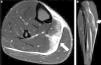

Su lesión suele confundirse con un cuadro de cólico renal, por lo que los pedidos de ecografías abdominales y de partes blandas habituales arrojan resultados negativos. El desgarro suele encontrarse a nivel de su inserción en la cresta ilíaca (fig. 3).

Desgarro del cuadrado lumbar izquierdo. Las secuencias ponderadas en STIR, planos (a) axial y (b) sagital, identifican una rotura parcial del músculo cuadrado lumbar a nivel de su inserción en la cresta ilíaca, adyacente al músculo paravertebral (flechas). La paciente consultó por la sospecha de un cálculo renal.

Se caracteriza por un incremento en la intensidad de señal del músculo, el cual puede estar asociado con un acortamiento del espacio entre el isquion y el trocánter menor (fig. 8). El dolor se produce por la irritación del nervio ciático, cuya ubicación es adyacente al cuadrado femoral, en relación posterior.

Desgarro del músculo cuadrado crural y síndrome isquiofemoral derecho. La secuencia ponderada en STIR, plano axial, revela un edema interfibrilar a nivel del músculo cuadrado crural (flecha). También se visualiza un ligero acortamiento del espacio entre la tuberosidad isquiática y el trocánter menor en el lado derecho, en comparación con el contralateral.